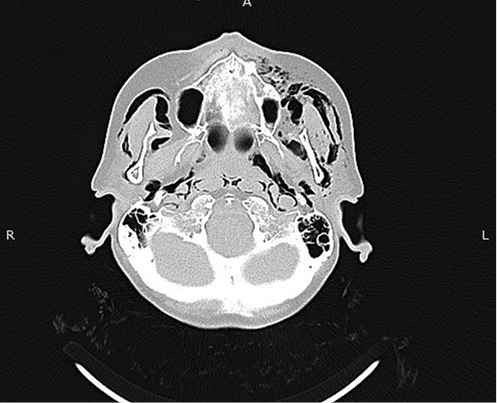

The chest X-ray was done immediately and did not present any abnormal signs, only small subcutaneous emphysema in the neck (Figure 1).

Figure 1. Chest X-ray